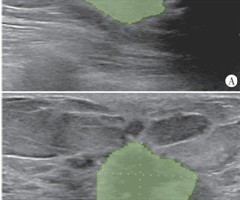

伴大汗腺分化的三阴性乳腺癌超声表现1例

[中图法分类号]R445.1;R737.9 [文献标识码]B 患者女,47岁。2年前行两癌筛查示左侧乳腺可疑团块,患者拒绝行穿刺活检,现来院复诊。体格检查:双侧乳房对称,局部皮肤无发红、水肿及橘皮样改变;双侧乳头无凹陷、无溢液,左侧乳腺2点...